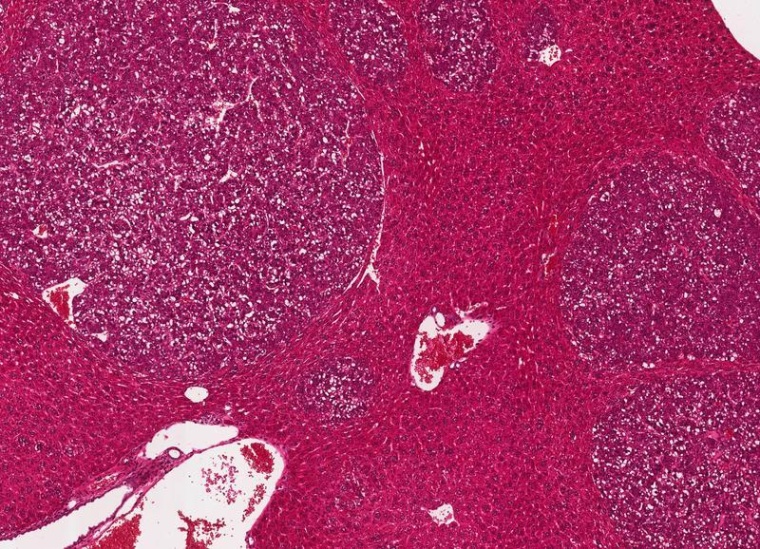

Leberkrebs-Forschung: Eisentod von Zellen könnte Schlüssel für neuartige Kombinationstherapien sein

Der Eisentod (Ferroptose) ist eine Form des gesteuerten Zellsterbens, mit dem der Körper kranke, defekte oder überflüssige Zellen abtötet. Dieser Prozess lässt sich nutzen, um die Wirkung einer Immuntherapie gegen Leberkrebs zu verstärken.

Dies haben jetzt Forschende des Georg-Speyer-Hauses, des Universitätsklinikums Frankfurt und der Goethe-Universität Frankfurt bei Mäusen zeigen können, die an Leberkrebs erkrankt waren. Die Kombinationstherapie wirkte auch gegen Darmkrebsmetastasen, die sich in der Leber angesiedelt hatten.